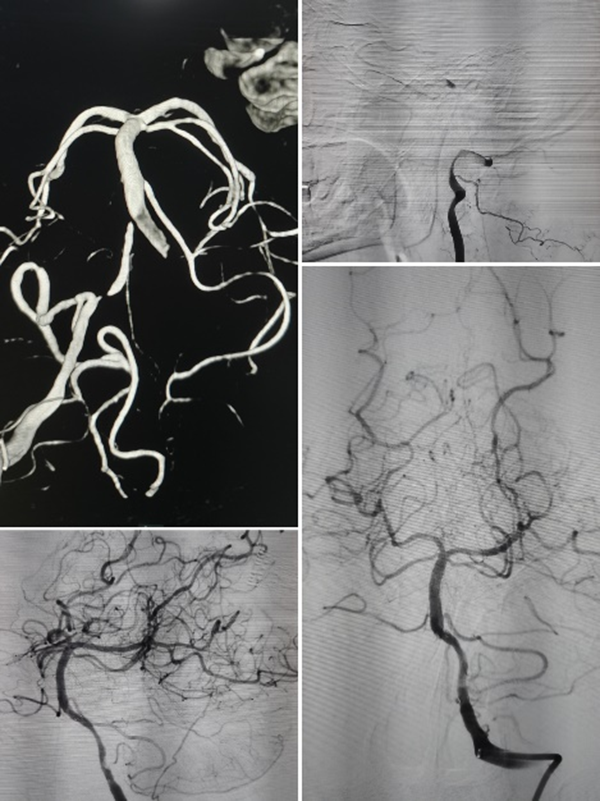

随着时间的推移,一例例复杂的全麻手术被成功完成:

青年卒中患者

全麻下椎动脉颅内段亚急性期闭塞再通术

基底动脉夹层管腔线样狭窄

全麻下支架植入术

全麻下大脑中动脉亚急性期闭塞再通术

高龄患者左颈内动脉C7段重度狭窄

全麻下支架术

高龄患者前交通不规则动脉瘤

全麻下支架辅助弹簧圈栓塞术

高龄老人椎动脉长段次全闭塞

全麻下多支架再通术

让我印象深刻的是位39岁的年轻男性患者,突发头晕伴右侧肢体麻木无力、言语不利,脑血管造影显示:椎动脉颅内段血管闭塞。患者病情复杂,血管闭塞节段长,而且血管条件差,开通闭塞血管的手术风险也相应增加,但如果选择保守治疗,将来发生严重卒中的风险非常高。

张主任带领团队对患者病情进行了细致分析,制定了详细的手术方案及预案,手术仅耗时40余分钟,夜里23:40,手术圆满结束。